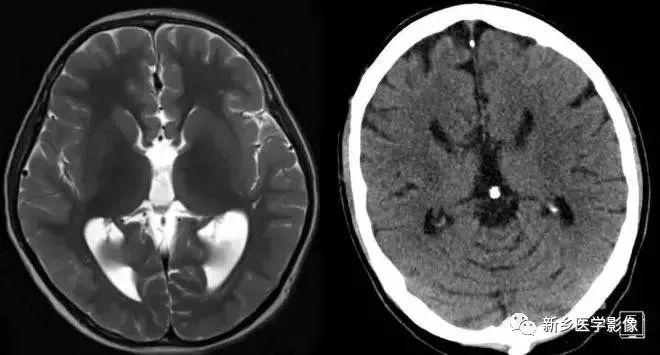

4.一侧室间孔阻塞

脑脊液主要产生于脑室的脉络膜丛。 当一侧室间孔阻塞时,同侧侧脑室脉络膜丛产生的脑脊液不能进入三脑室,脑脊液在侧脑室内聚积,CT和MR检查表现为一侧侧脑室扩大,扩大明显时可有中线结构向对侧移位,主要原因有室间孔附近的肿瘤、囊肿、囊虫及炎性粘连。 确定一侧侧脑室扩大为室间孔阻塞所致的要点包括:一侧侧脑室扩张明显,有张力.透明隔向对侧移位;扩一大的侧脑室周围没有能够导致该侧侧脑室扩大的其他可以解释的原因。